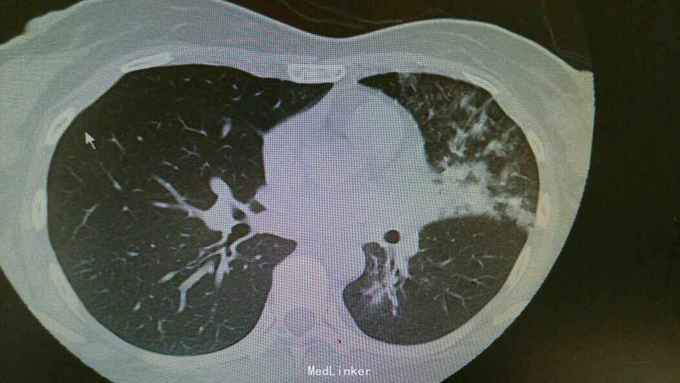

主诉:发热伴咳嗽咳痰6天。 病史:患者6天前无明显诱因出现发热,最高体温39.3度,伴有咳嗽,咳痰,咳黄色粘液痰,无畏寒寒战,无头晕头痛,为求治疗,入住我科。

查体:双肺呼吸音粗,双下肺可闻及湿罗音。心腹无异常。 辅查:双肺炎症,左侧可见多发斑片状,渗出实变影,边缘模糊,部分邻近胸膜,粘连。

诊断:肺炎支原体费炎。 治疗:入院予以抗感染,止咳化痰等治疗。治疗后复查胸片,左中下肺炎症好转。